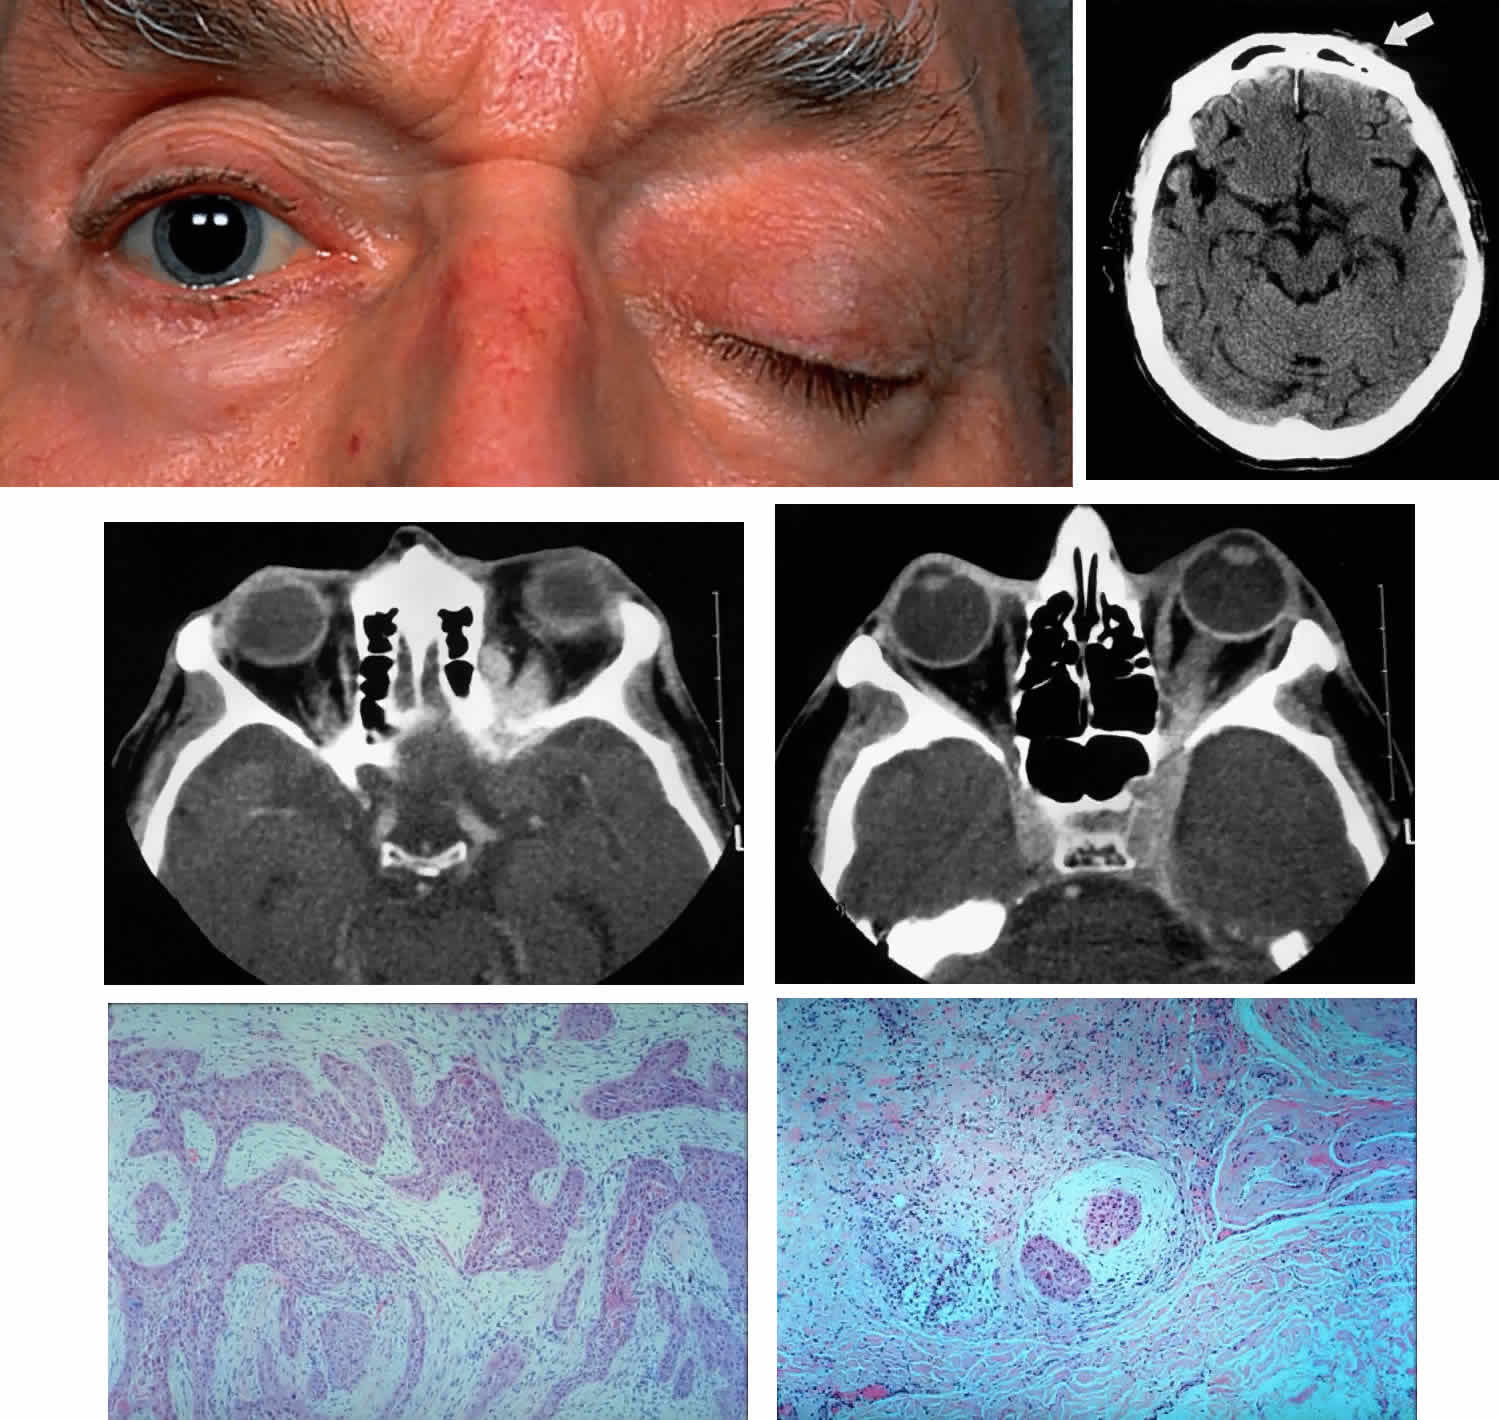

The clinical signs of squamous cell carcinoma (mean, 1 year) develop faster than the signs of basal cell carcinoma, consisting of focal hyperkeratotic lesions that slowly extend and ulcerate. They are more common at the lid margin and in the lower lid versus the upper lid, by a ratio of 1.4:1.56 Rarely, papillary forms may be seen. Orbital extension of squamous cell carcinoma is usually preceded by a history of chronic and repeated recurrence of lesions following treatment or long-term neglect by the patient (Fig. 7). Once the orbit is invaded, the tumor tends to spread along fascia and fatty planes relatively rapidly compared with basal cell carcinoma. Perineural invasion may occur and is associated with pain or ophthalmoplegia (Fig. 8).57–60 Also in contrast to basal cell carcinoma, squamous cell carcinoma is capable of metastasis, usually to the regional preauricular or submandibular lymph nodes. The incidence of regional spread varies from 1% to 21%, but is generally closer to the lower figure. In a review of large series documented in the literature, the overall mortality rate was found to be approximately 15%.56 Management of squamous cell carcinoma of the lid is usually surgical, with care being taken to obtain adequate controlled margins with the use of frozen sections or Mohs' technique. Fitzpatrick and associates61 reported a control rate of 93% with radiotherapy; however, squamous cell carcinoma is thought to be less sensitive to radiotherapy than basal cell carcinoma, so higher doses are usually recommended. For deep orbital invasion, radical therapy is indicated; this may constitute either exenteration or radical radiotherapy, according to the circumstances outlined in the discussion on basal cell carcinoma.

Fig. 7. A 61-year-old chronic alcoholic man presented with a fungating, putrefying, left temporal mass(inset) that extended into the adjacent orbit and flattened the globe, as shown on coronal CT scan. It proved to be a squamous cell carcinoma of the skin associated with cervical and mediastinal adenopathy. He underwent radical local radiotherapy, which led to regression of the local lesion. (Rootman J, Ragaz J, Cline R, Lapointe JS: Metastatic and secondary tumors of the orbit. In Rootman JR (ed): Diseases of the Orbit: A Multidisciplinary Approach, pp 405–427. Philadelphia, JB Lippincott, 1988.)

Fig. 8. A 73-year-old man treated 3 years previously with excision of a squamous cell carcinoma in the left supraorbital region had recurrence of tumor, which was again excised. He developed progressive pain and tingling in the forehead, vertical diplopia, and finally general malaise lasting 18 months, ultimately requiring hospitalization. He was treated with corticosteroids for presumed Tolosa-Hunt syndrome, showed minimal improvement, and was discharged. Over a 2-month period, he developed decreased vision, ptosis, and bulging of the eye. On presentation he had vision of 20/80 with a relative afferent pupillary defect. There was hypesthesia in the distribution of cranial nerve V1 and hyperesthesia in V2. He had a palpable fixed cord in the forehead in the distribution of the supraorbital nerve, complete ptosis, ophthalmoplegia, and 7 mm of proptosis (A). CT scan showed local infiltration along the supraorbital nerve (B, arrow), with extension of a soft tissue mass along the orbital roof to the orbital apex (C), through a widened superior orbital fissure, and into the cavernous sinus (D). An orbital biopsy revealed cords of squamous cells (E) (H & E, × 80) and evidence of infiltration inside a small branch nerve sheath (F) (H & E, × 80). A single fraction of 10 Gy was given as palliative treatment for pain control.